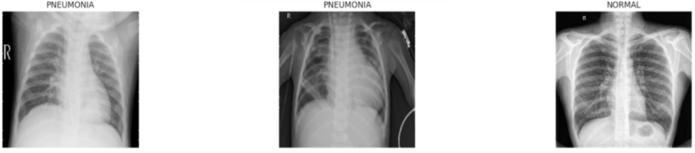

Theefficacyofadeeplearningsystemisinextricablylinked tothequalityandorganizationofitsinputdata.Theproject utilizesawell-curateddatasetconsistingoflabelledchestXrayimages,sourcedtypicallyfrompublicarchivessuchas Kaggle’s Chest X-ray dataset or the National Institutes of Health(NIH)dataset.1 Thisdatasetispartitionedintothree distinctsets:Training,Validation,andTest,ensuringthatthe final performance evaluation is conducted on completely unseendata.

A critical challenge in medical datasets, particularly for binary classification like pneumonia detection, is class imbalance. The following table provides a hypothetical representationofthelikelydistribution,illustratingahigh imbalancewherepneumoniacasessignificantlyoutnumber normalcases,especiallyinthetrainingset,whichiscommon inclinicaldatacollection.

Tostandardizethevisualinputsandoptimizethemfordeep learning, all images undergo a rigorous preprocessing pipeline. Standardization involves resizing all images to a uniformdimension,specifically224*224pixels,whichisthe required input size for the classification backbones (ResNet50andDenseNet121).Additionally,pixelintensity values are normalized to the range to ensure consistency across the dataset, which improves model convergence speedandstability.

Data augmentation is exclusively applied to the training dataset to enhance model robustness and prevent overfitting. This involves applying geometric and photometric transformations designed to simulate the variationsencounteredinreal-worldclinicalsettings,such as slight positioning differences or variations in imaging quality.Specifictransformationsincluderotation(upto10 Degree),shiftsinwidthandheight(upto6%),zoom(upto 8%),andhorizontalflipping.